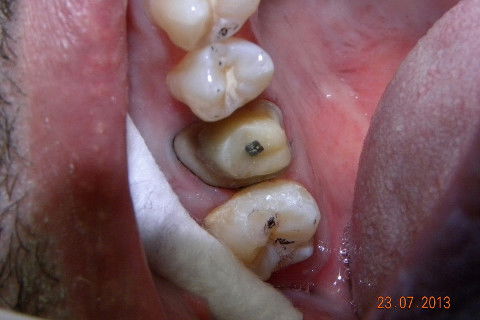

1ª CONSULTA: remoção de tecido cariado e exposição da entrada dos canais.

Caso de fratura de um trabalho protético preexistente, não sei qual e nem o paciente soube informar. Na minha opinião caso indicado para pinos metalicos rosqueáveis, muitos colegas condenam e indicam para esse caso pino metálico fundido. Creio que o fato de você fazer o preenchimento do núcleo com resina e depois cimentar com um cimento resinoso onde vai haver adesão química nas duas partes, formando um corpo único entre núcleo e coroa, ofereça uma resistência muito maior do que uma linha de cimentação onde a retenção é apenas mecânica. Continuando... 1ª CONSULTA: Pinos metálicos rosqueáveis, preenchimnto em resina, coroa provisória e moldagem com sil de adição (para qe possamos vazar o troquel e no mesmo molde o modelo para aplicação da cerâmica. 2ª CONSULTA: restauração de uma cárie no dente 17 (eu sei que era para ter feito na 1ª consulta por conta do ponto de contato, mas não deu tempo) e cimentação com cimento resinoso da 3M e caso encerrado. A radiografia não é desse caso, mas de uma caso igualzinho, a única diferença foi que envolveu cirurgia periodontal, veja como há a formação de um corpo único entre, núcleo e coroa. Um abraço. Jadson.